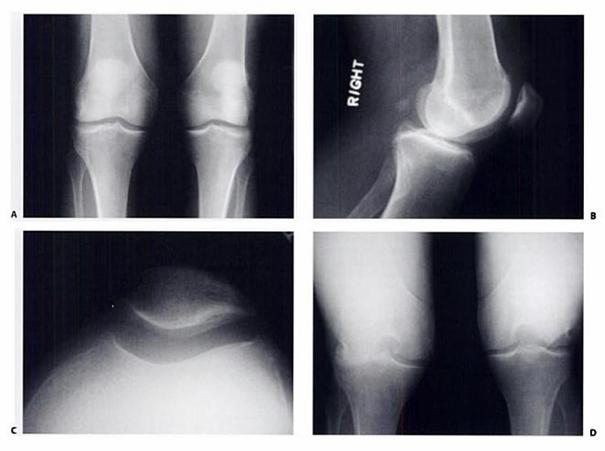

Fig.15. A- radiografie antero-posterioara ; B- radiografie laterala; C- vedere axiala a patelei; D- radiografie

Scorul Outerbridge:

I. Inmuierea si aparitia de cavitati intracartilaginoase,

II. Aparitia fisurilor,

III. Fisuri si fasciculari ale cartilajului,

IV. Denudarea osului subcondral.